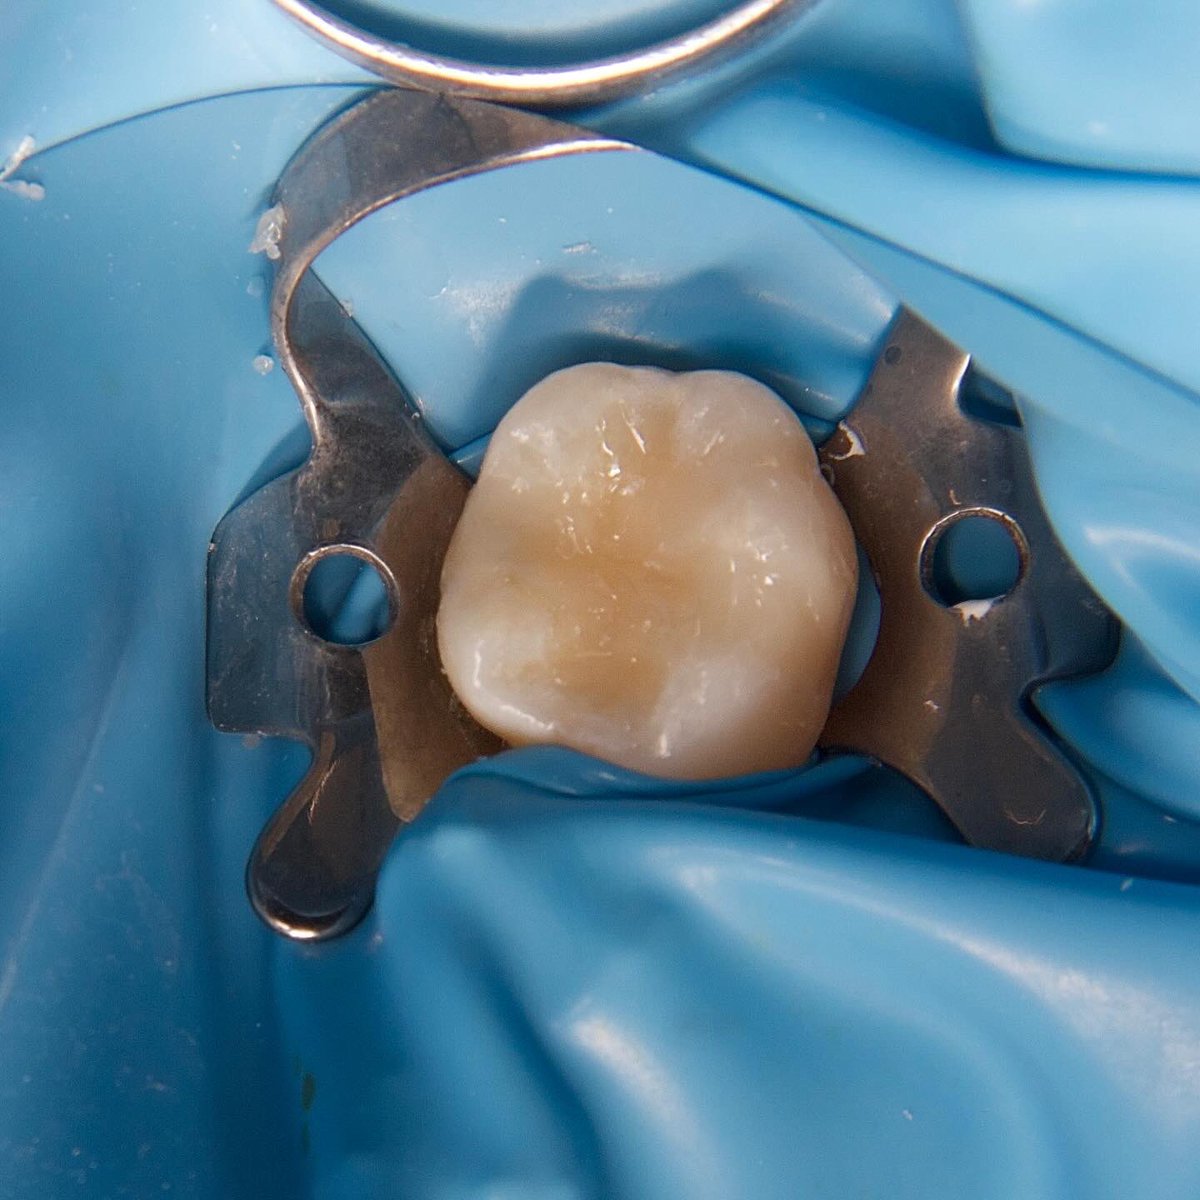

E-max Endocrown for #36 😍🤍 All procedure done under rubber dam IDS , surface treatments and cementation تلبسية جزئية من مادة الخزف للحفاظ على الضرس بعد علاج العصب 🦷

E-max Endocrown for #36 😍🤍

All procedure done under rubber dam

IDS , surface treatments and cementation

تلبسية جزئية من مادة الخزف للحفاظ على الضرس بعد علاج العصب 🦷